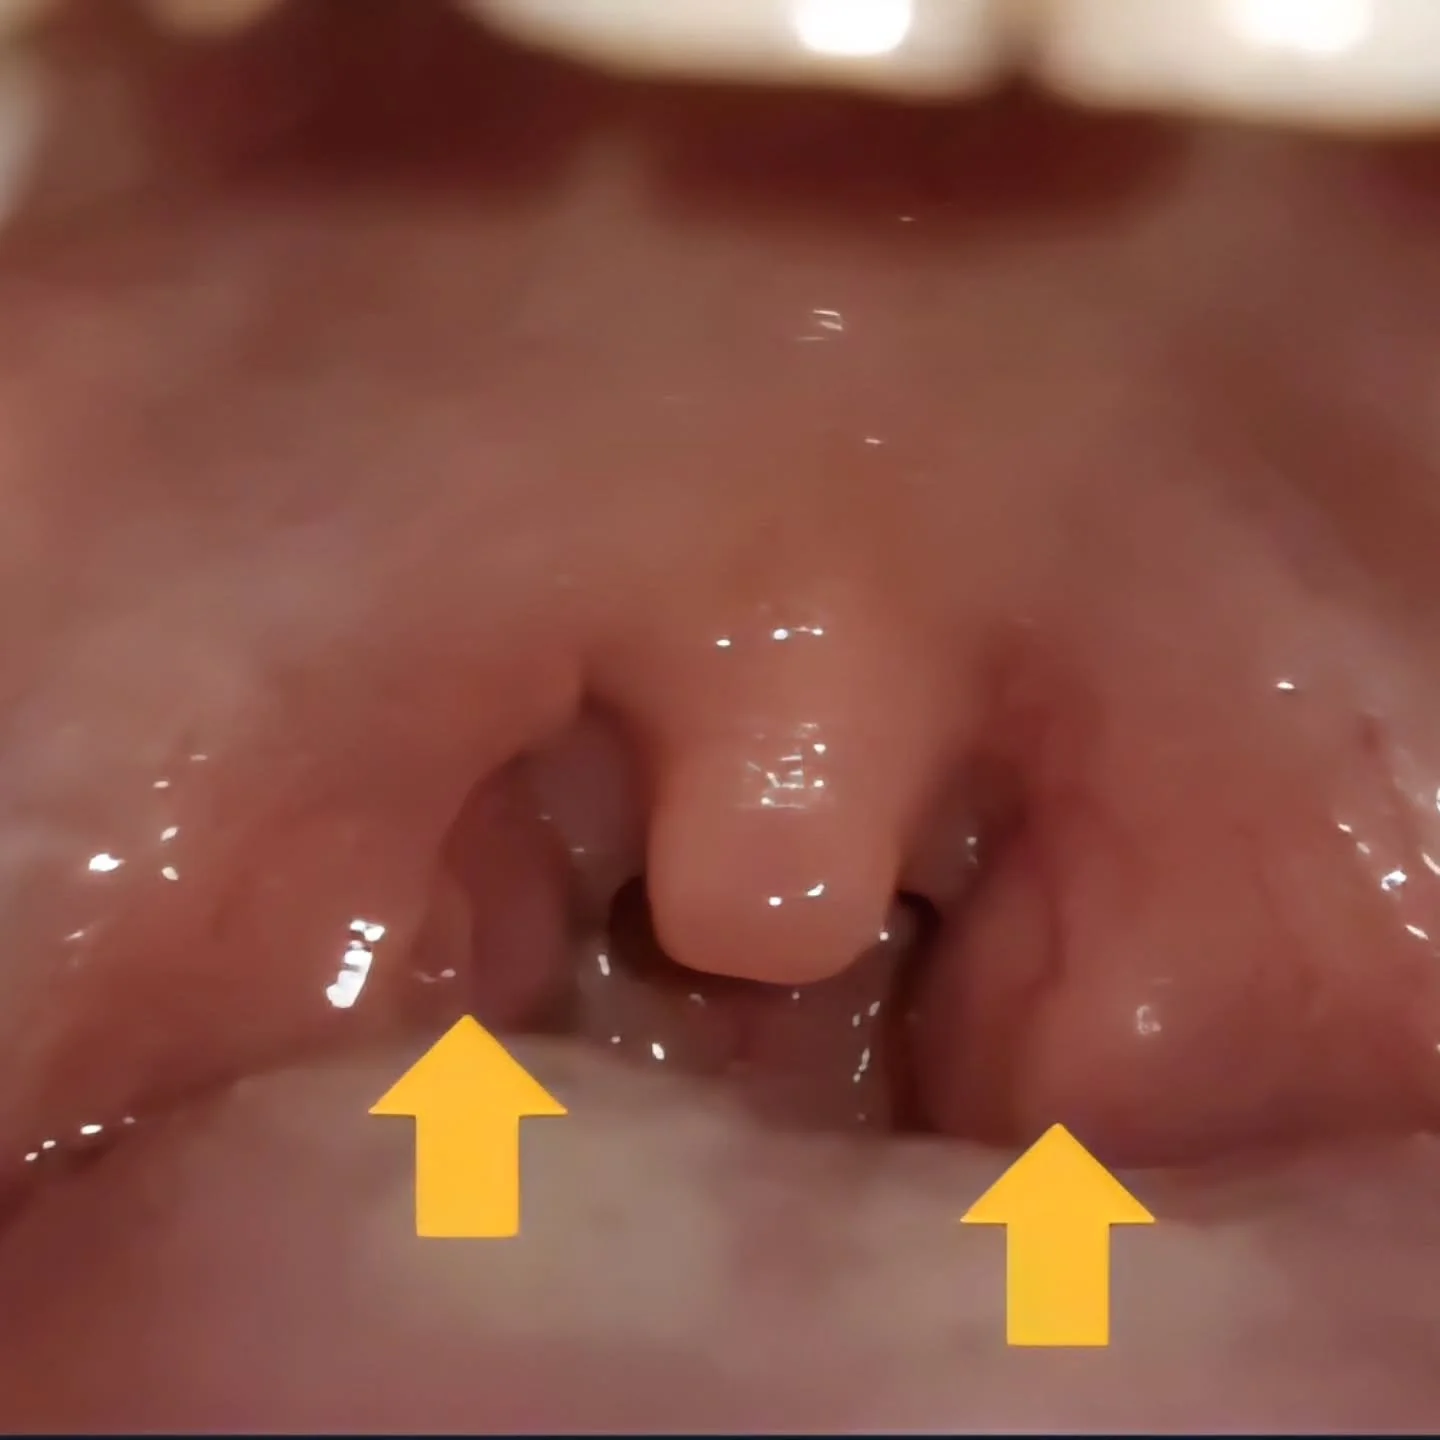

The Hidden Impact of Tongue Ties on Your Entire Body.

I remember thinking this exact thought after learning that I β a veteran dental provider β had an unaddressed and undiagnosed tongue tie until just a few years ago.

How could I go my whole life seeing multiple dental professionals, going through rigorous clinical evaluations, and never have my tongue tie mentioned?